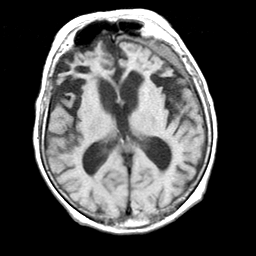

Pick's Disease, MR Study mr-t1 -- Slice #11

[Home][Help][Clinical] Slice 11